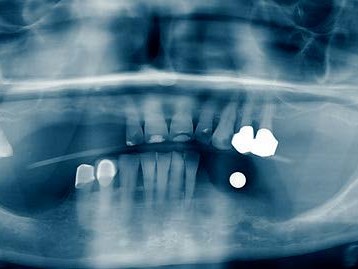

Eine 72-jährige Patientin stellte sich mit einer teleskopierenden Arbeit vor, die seit über zehn Jahren bestand. Der Teleskop-Pfeilerzahn 33 (Abb. 1) war nach Wurzelkanalbehandlung (Abb.2) aufgrund einer rezidivierenden apikalen Ostitis entfernt worden (Abb. 3). Hauszahnärztlich war ein Heil- und Kostenplan mit dem Ziel erstellt worden, sämtliche Unterkieferzähne teleskopierend zu versorgen. Dieser Vorschlag war der Patientin zu invasiv und überstieg vor allem ihre wirtschaftlichen Möglichkeiten als Rentnerin. Der Vorschlag, die bestehende Teleskoparbeit unter Insertion eines Implantates in regio 33 mit der Versorgung über das industriell gefertigte SynCone-Konuskronenprinzip zu erhalten, erschien der Patientin als eine einfache, gute und auch wirtschaftlich für sie realisierbare Alternative sinnvoll. Daraufhin wurde in regio 033 im Rahmen der Spätimplantation ein ANKYLOS C/X-A-Implantat (Durchmesser 3,5 und Länge 14 mm) inseriert (Abb. 4). Nach einer Einheilungsphase von zwei Monaten erfolgte die Implantatfreilegung. Bei der Implantatinsertion zeigte das Implantat einen Osstell-Messwert von 76 ISQ, bei Implantatfreilegung einen ISQ-Messwert von 82. Nach Überprüfung der Parallelität kam ein ANKYLOS SynCone C/ Aufbau 5° der Gingivahöhe 4,5 zur Anwendung. Dieser wurde mit 15 Ncm Drehmoment angezogen. Chairside wurde mit Unterstützung durch den Zahntechnikermeister vor Ort die ANKYLOS Degulor-Konuskappe SynCone 5° mit Retentionen eingearbeitet. Es erfolgten Nachkontrollen halbjährig. Bei der Zweijahres-Nachschau berichtete die Patientin unaufgefordert, dass sie mit der Rettung ihrer schon über zehn Jahren bestehenden Teleskoparbeit die richtige Entscheidung getroffen hatte und dass diese noch bestens in Funktion sei, wie diese selbst demonstrierte (Abb. 5-7).